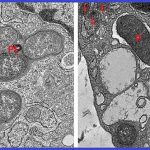

SLA-immaagine: cellule altamente degradative (scure) nel midollo spinale sono state identificate come motoneuroni. Crediti: Kazuhide Asakawa, National Institute of Genetics.

In uno studio pubblicato su Nature Communications, Kazuhide Asakawa e colleghi hanno utilizzato l’imaging a risoluzione di singole cellule in pesci zebra trasparenti per dimostrare che i grandi motoneuroni spinali che generano forti movimenti del corpo e sono più vulnerabili nella SLA, operano sotto un carico costante e intrinseco di degradazione di proteine ​​e organelli.

Le osservazioni del team rivelano che i grandi motoneuroni spinali, deputati a generare potenti movimenti corporei e particolarmente sensibili alla patologia SLA, sopportano un carico intrinseco e continuo legato alla degradazione di proteine ​​e organelli. Questi neuroni mostrano costantemente un’elevata attività basale in tre vie cellulari critiche: autofagia, degradazione mediata dal proteasoma e risposta proteica non ripiegata. Insieme, questi meccanismi costituiscono le principali modalità cellulari per mantenere il controllo di qualità di proteine ​​e organelli, suggerendo che i grandi motoneuroni siano costantemente impegnati nella gestione di un esteso stress proteostatico.